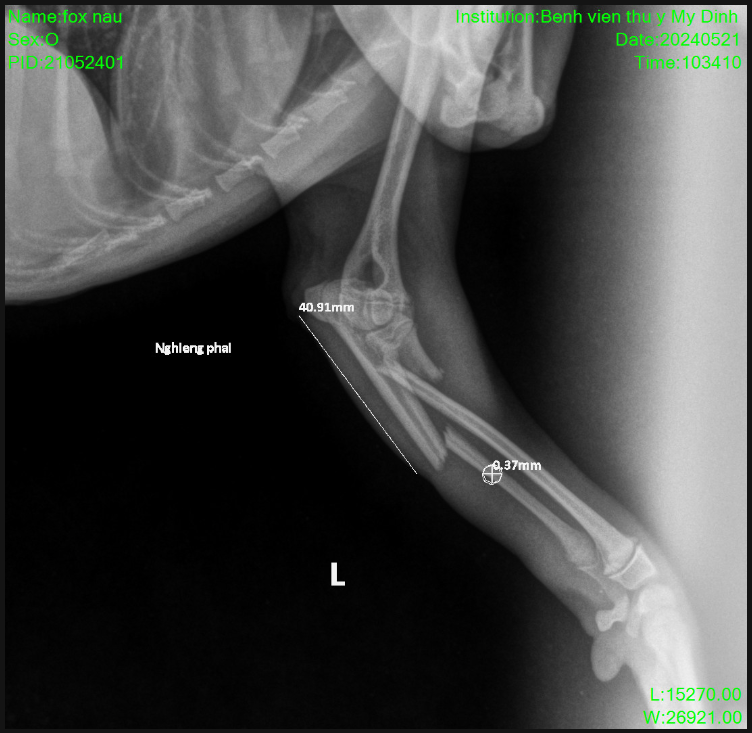

Chó mèo bị gãy xương, rạn xương là việc thường hay xảy ra trong cuộc sống hằng ngày của chúng ta. Nguyên nhân gây chấn thương được thống kê cao nhất tại các phòng khám, bệnh viện thú y là do liên quan đến tai nạn, sự cố ngã hay những vụ xung đột giữa…